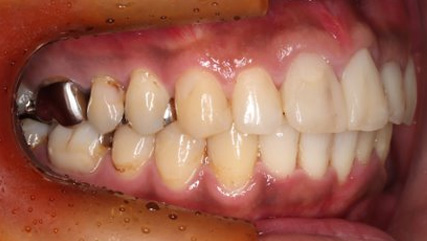

治療前

治療終了前